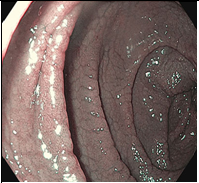

Целиакия-это хроническое мультифакториальное заболевание,  вызванное повреждением ворсинок тонкой кишки некоторыми пищевыми продуктами, содержащими определённые белки: глютен (клейковину) и близкие к нему белки злаков (авенин, гордеин и др.)и приводящее к плотной инфильтрации лимфоцитов в проксимальном отделе тонкой кишки.  Целиакия-это хроническое мультифакториальное заболевание,  вызванное повреждением ворсинок тонкой кишки некоторыми пищевыми продуктами, содержащими определённые белки: глютен (клейковину) и близкие к нему белки злаков (авенин, гордеин и др.)и приводящее к плотной инфильтрации лимфоцитов в проксимальном отделе тонкой кишки. Гистологическое заключение: целиакия тип 3b за Marsh–Oberhuber

Благодаря усовершенствованию видеоэндоскопов, которые используются в повседневной практике, включая внедрение узкополосной визуализации (NBI) и ближнего фокуса, подробное исследование слизистой оболочки двенадцатиперстной кишки дает точный метод оптической диагностики (2–4). Эндоскопически видимыми признаками целиакии являются зубчатые дуоденальные складки, бороздки и трещины (см Таблица ниже). Это контрастирует со здоровой тканью, которая покрыта ворсинками, похожими на пальцы, которые обеспечивают большую площадь поверхности для поглощения питательных веществ. При целиакии ворсинки обычно намного короче и менее выражены, чем на здоровой слизистой оболочке.

Под эндоскопией, рисунок ворсинок может быть дополнительно улучшен закапыванием воды, и этот подход регулярно используется при оценке заболеваний как двенадцатиперстной, так и тощей кишки. Водная иммерсия проста, включает удаление воздуха из просвета двенадцатиперстной кишки с последующей инъекцией 90–150 мл воды. После этого признаки целиакии, такие как зубчатые дуоденальные складки, бороздки и трещины, могут быть легко визуализированы. Таким образом, этот метод позволяет с высокой точностью диагностировать участки повреждения ворсинок двенадцатиперстной кишки (5,6).

Эндоскопические маркеры целиакии включают в себя полное отсутствие или снижение высоты складок слизистой оболочки двенадцатиперстной кишки, хаотичность складок, вид «микроузелков» по типу «крупы», изъязвления и фиссуры слизистой у взрослых больных, видимый сосудистый рисунок. Однако, специфичность этих признаков неоднозначна, они лишь указывают на возможность атрофических процессов в слизистой оболочке тонкой кишки и такие же изменения могут отмечаться при болезни